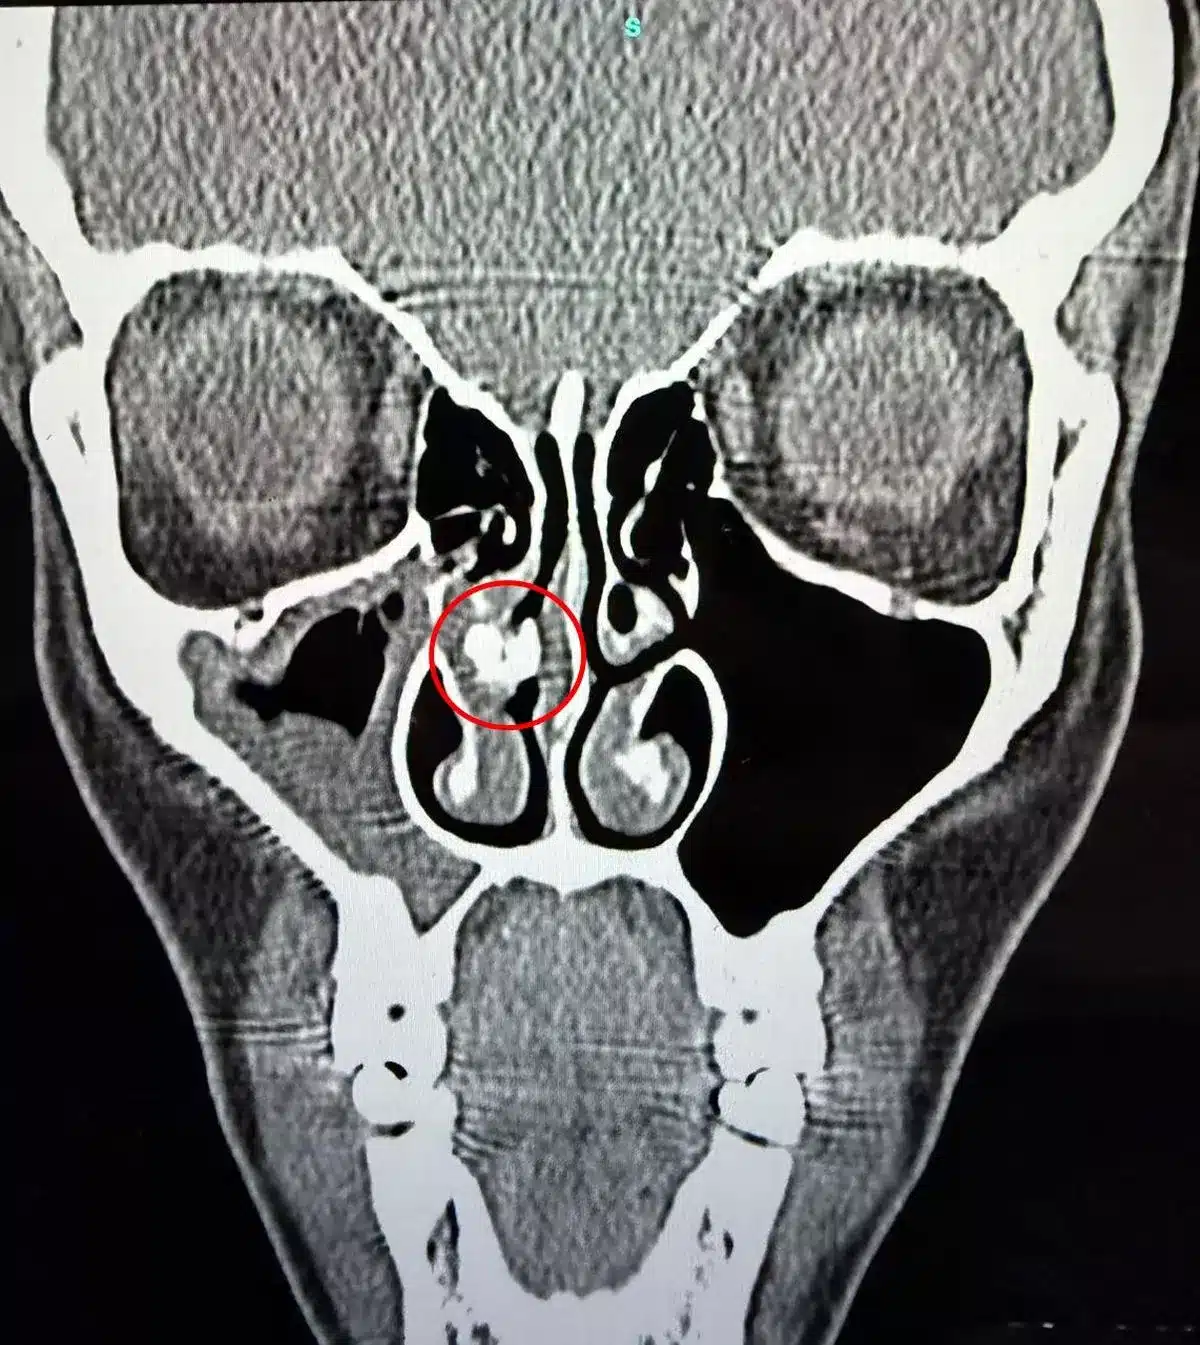

แพทย์ได้ทำการตรวจอย่างละเอียดและส่งตัวเธอไปทำซีทีสแกน จนพบความผิดปกติที่ระบุว่าเป็นจุดที่มีหินปูนเกาะ หรือนิ่วในจมูก แพทย์จึงตัดสินใจใช้กล้องส่องและใช้เครื่องมือพยายามคีบสิ่งอุดตันดังกล่าวออกมา โดยใช้เวลานานเกือบ 1 ชั่วโมง ท่ามกลางความลุ้นระทึกว่าสิ่งที่อยู่ข้างในคืออะไรกันแน่

วินาทีที่คีบออกมาได้สำเร็จ ทั้งหมอและคนไข้ต่างตกตะลึง เมื่อพบว่าก้อนปริศนานั้นคือเศษเทปกาวที่ม้วนขยุ้มรวมกันอยู่ เมื่อนำเรื่องนี้ไปบอกกล่าวกับครอบครัว จึงได้ความว่าน่าจะเป็นไปได้ที่สุดว่า เทปกาวชิ้นนี้น่าจะตกค้างอยู่ในโพรงจมูกของเธอมาตั้งแต่ปี 1990 หรือเมื่อ 35 ปีก่อน ตอนที่เธอยังเป็นทารกแรกเกิดและต้องรักษาตัวในห้อง ICU ซึ่งแพทย์ในตอนนั้นอาจใช้เทปยึดสายยางช่วยหายใจ แล้วเกิดผิดพลาดจนเทปหลุดเข้าไปติดค้างอยู่ภายใน